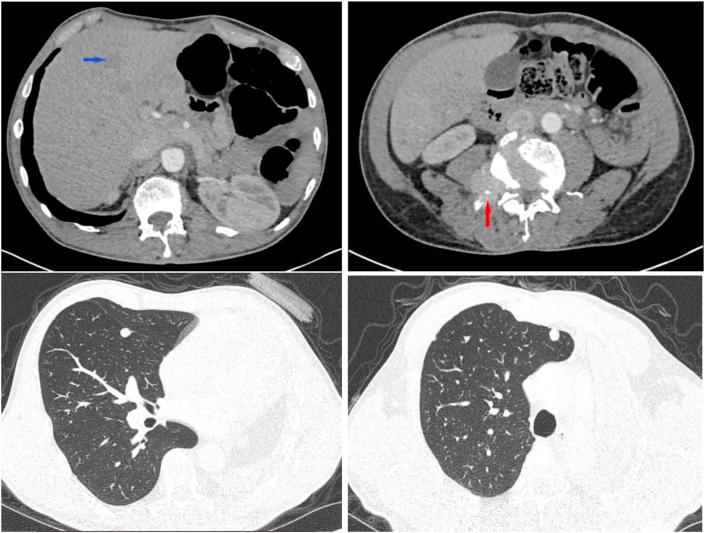

Typical carcinoid tumors of the lungs carry an excellent prognosis after complete surgical excision. However, recurrence of these cancers remains poorly described in the literature and may occur many years after surgery. We report a case of carcinoid tumor of the lung. Clinical presentation and follow-up were uneventful. The 55 years old patient had got a surgical removal of a huge typical carcinoid tumor of the left lung. A left pneumonectomy with a mediastinal lymph node resection were performed. Thirteen years later, paraneoplastic acromegaly revealed a pulmonary and extrapulmonary recurrence of the tumor. We prescribed a chemotherapy regimen including Cisplatin and Etoposide. Endocrine paraneoplastic syndromes are related to mutations in specifically known genes. Several mutations may become a promising therapeutic target in the future. In the case of neuro-endocrine pulmonary tumors, authors described BCOR gene mutation as an oncogenic development inducer and an eventual generator of ectopic tumoral secretions. The more we get familiar with carcinoid tumor mutations, the closer we get to targeted therapy for non-resectable tumors.

典型的肺类癌肿瘤在完整手术切除后预后良好。然而,这些癌症的复发在文献中描述较少,且可能在手术后多年发生。我们报告一例肺类癌肿瘤病例。临床表现及随访过程均无异常。这位55岁的患者接受了左肺巨大典型类癌肿瘤的手术切除。进行了左全肺切除术及纵隔淋巴结切除术。十三年后,副肿瘤性肢端肥大症提示肿瘤出现肺内及肺外复发。我们开具了包括顺铂和依托泊苷的化疗方案。内分泌副肿瘤综合征与特定已知基因的突变有关。若干突变可能在未来成为有前景的治疗靶点。对于神经内分泌性肺肿瘤,作者将BCOR基因突变描述为致癌发展诱导因素及异位肿瘤分泌物的最终产生因素。我们对类癌肿瘤突变了解得越多,就越接近对不可切除肿瘤的靶向治疗。